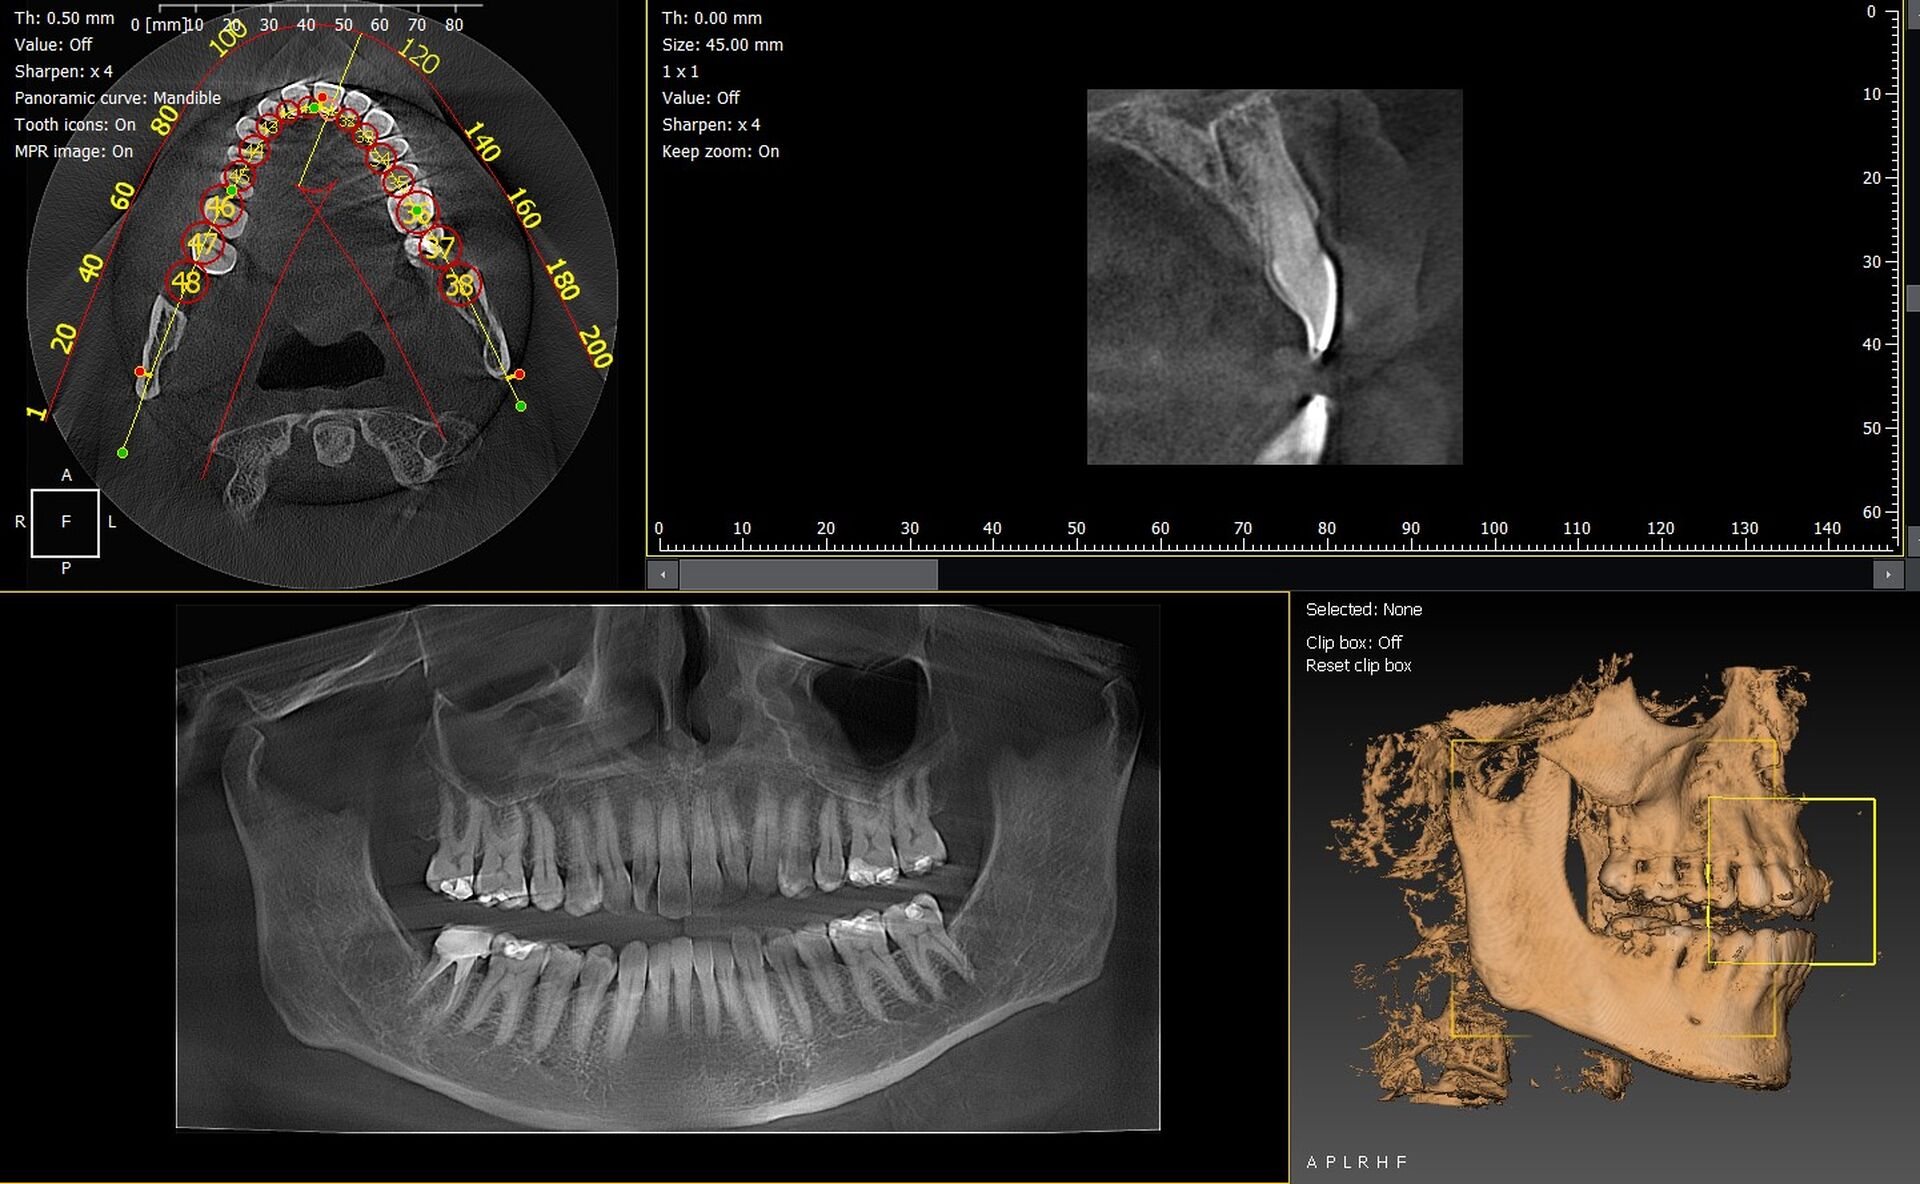

Les cabinets dentaires de Nice et du département des Alpes-Maritimes (06) modernisent leur plateau technique pour répondre aux exigences cliniques actuelles. Les panoramiques CBCT 3D VistaVox de Dürr Dental et l’Owandy I-Max 3D font partie des solutions d’imagerie les plus performantes, garantissant des diagnostics précis et une qualité d’image optimale.

VistaVox 3D : imagerie haute précision

Le VistaVox offre un volume d’imagerie conçu pour l’arcade dentaire, idéal pour :

• l’implantologie,

• l’endodontie,

• les bilans chirurgicaux,

• l’analyse des ATM.

Sa haute résolution et son positionnement simple améliorent la fiabilité du diagnostic.